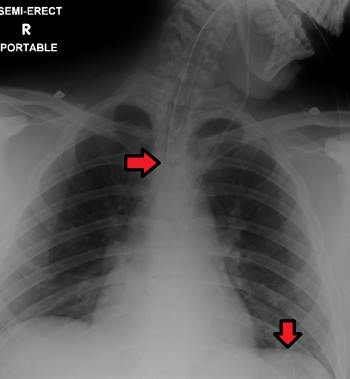

Se si verificano questi segni, il sondino deve essere immediatamente rimosso fino al ripristino della normale respirazione. Vedere la Figura 5.6 [17] per un'immagine di una radiografia che mostra il corretto posizionamento di un sondino enterale nello stomaco, come indicato dalla freccia rossa inferiore. (Questa radiografia mostra anche un tubo endotracheale posizionato correttamente nella trachea come indicato dalla freccia in alto.) Dopo la verifica radiografica, il tubo deve essere contrassegnato con nastro adesivo e/o un pennarello indelebile per indicare la misurazione sul tubo nel punto in cui il sondino di alimentazione entra nelle narici o penetra nella parete addominale.

Questo numero sul tubo nel punto di ingresso deve essere documentato nella cartella clinica e comunicato durante i rapporti di passaggio di consegne. All'inizio di ogni turno, l'infermiere deve valutare se la marcatura incrementale o la lunghezza esterna del tubo sono cambiate. Se si osserva una variazione, test al letto del paziente come la visualizzazione o il test del pH dell'aspirato del tubo possono aiutare a determinare se il tubo si è spostato. In caso di dubbio, il fornitore deve essere informato e una radiografia deve essere ripetuta per confermare la posizione del tubo. [18]

Figura 5.6 Verifica del posizionamento tramite raggi X